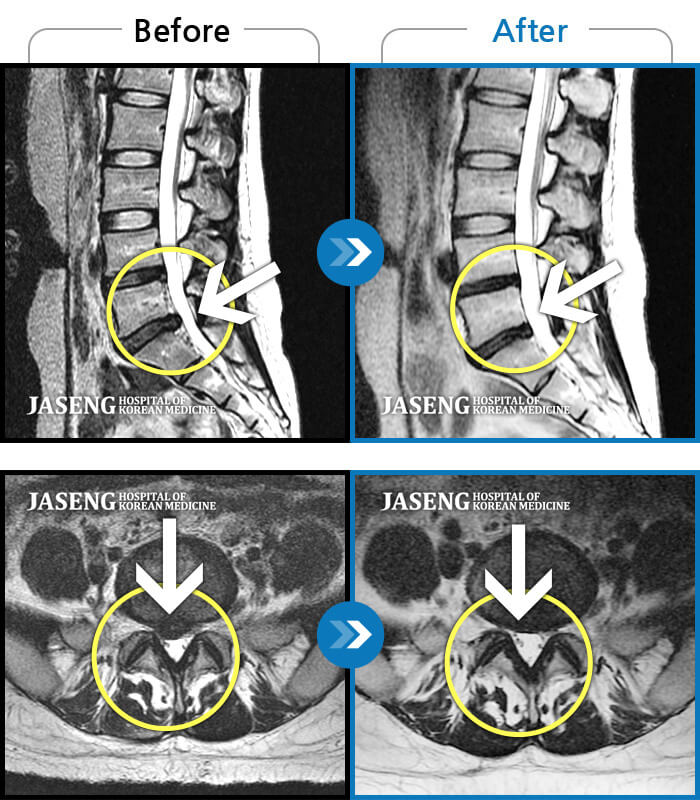

추간판 탈출증이라 불리는 허리디스크 증상은 크게 3단계로 나눌 수 있어요. 1단계는 내부 섬유륜이 파열하여 수핵이 빵빵한 상태, 2단계는 섬유륜 전체가 파열되어 수핵이 탈출하는 단계, 3단계는 완전히 탈출해 버린 단계입니다.

단계마다 느끼는 증상들이 조금씩 다른데요. 디스크의 보호막이 약간 찢어졌고 디스크가 약간 튀어 주변의 신경 뿌리에 닿으면 염증성의 통증이 발생하기 시작하면서 점점 증상이 심해지면 디스크의 파열은 골수를 이루고 있는 핵이 튀어나오면서 신경에 대한 물리적 압박을 가하고 참을 수 없는 아픔을 유발하게 돼요.